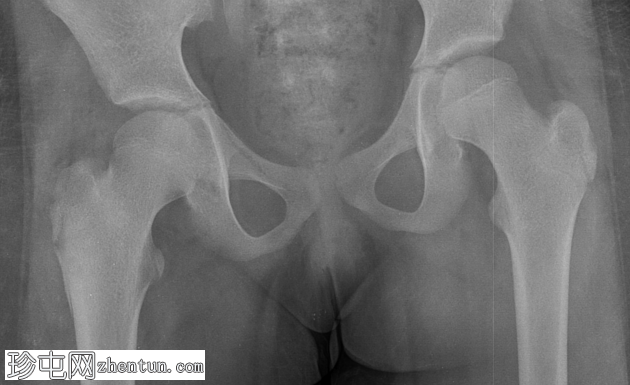

X光片

右侧股骨转子下边界不清的透亮区,伴有层状骨膜反应。